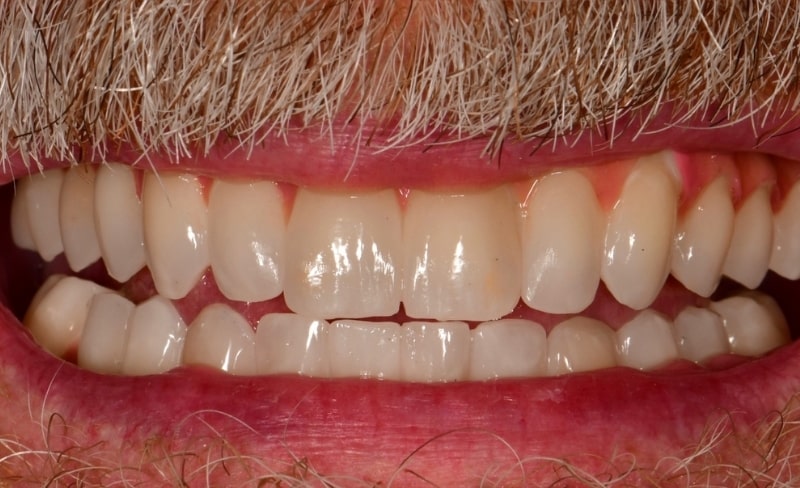

Upper and lower all-on-4 dental implants to restore function and aesthetics.